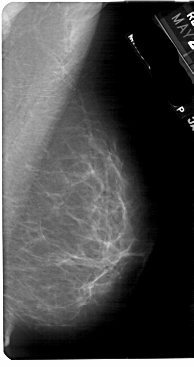

A_1833_1.RIGHT_MLO

RIGHT_CC LINES 5491 PIXELS_PER_LINE 2986 BITS_PER_PIXEL 12 RESOLUTION 43.5 NON_OVERLAY